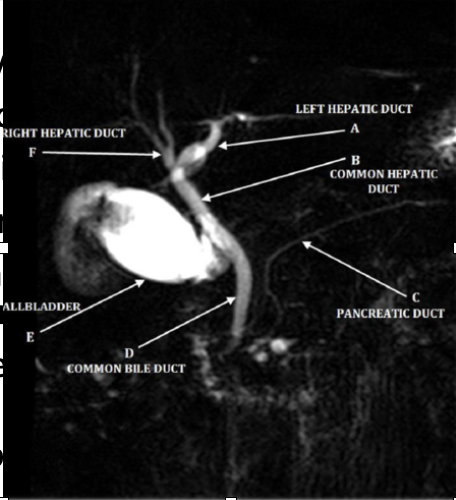

ERCP

-invasive, involves sedatives, radiation and more costly

-can cause pancreatitis, infection, bleeding

-diagnostic and therapeutic (stent, remove gallstones)

-gold standard for diagnosis of biliary obstruction

MRCP

-noninvasive, without anesthesia or radiation, cheaper

-improved visualization

-contraindicated with pacemakers and cochlear implant

-diagnostic but NOT therapeutic (delays treatment)